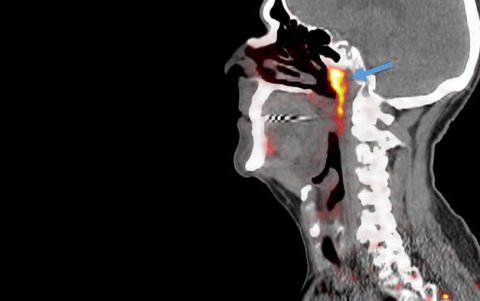

Cuando estaban en ello, notaron dos glándulas, de unos cinco centímetros de largo. Estaban discretamente ocultas, específicamente donde las orejas se conectan a la garganta, cerca de la base del cráneo.

Imagen del estudio inicial en el que se identifica el que sería el nuevo órgano.

Ahora bien, de confirmarse este hallazgo, estas glándulas recién descubiertas se suman a otros tres conjuntos de glándulas salivales más grandes. Se ubican, de acuerdo a Science, debajo de la mandíbula, debajo de la lengua y un tercero cerca de las orejas.